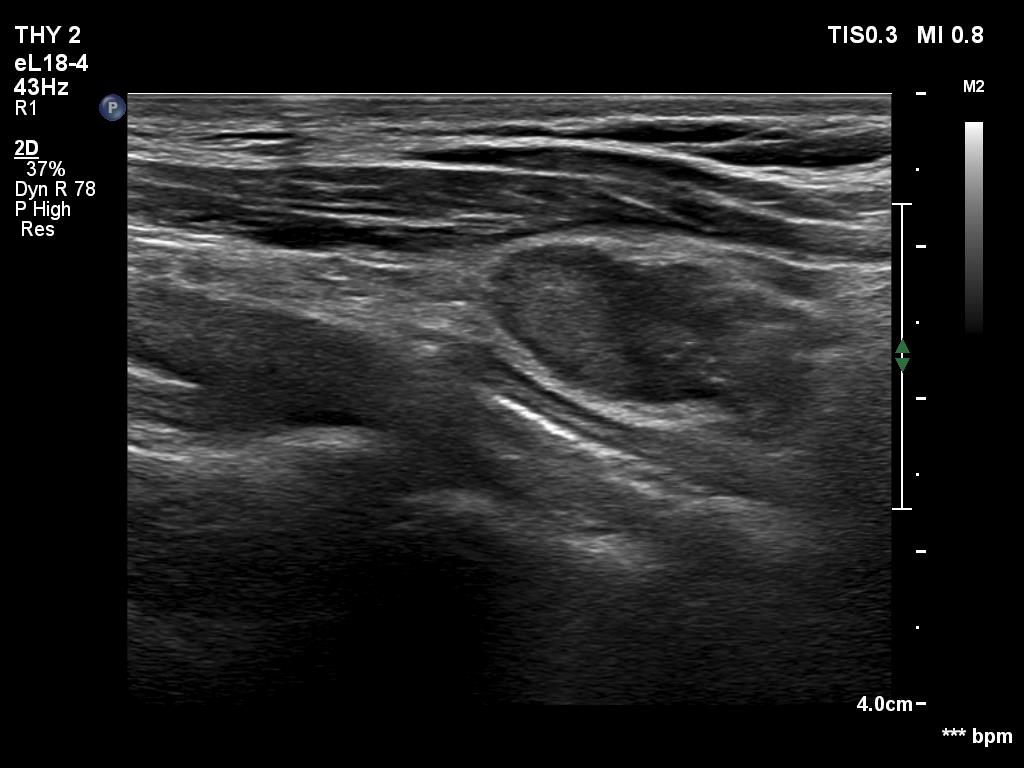

Follow-up investigation 8 years later (ultrasonographic picture 5)

Left thyroid bed, another longitudinal scan.